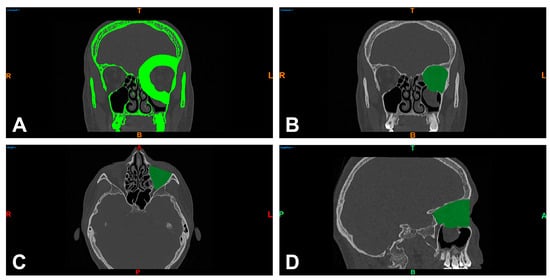

| n = 104 | PDS Foil | Titanium Mesh | ||||

|---|---|---|---|---|---|---|

| Volume (cm3) | Fold Change in Preoperative Values | Volume (cm3) | Fold Change in Preoperative Values | |||

| Preoperative | Postoperative | Preoperative | Postoperative | |||

| Mean | 30.60 | 30.09 | 0.98 | 32.65 | 29.69 | 0.91 |

| Median | 30.57 | 29.83 | 0.98 | 34.37 | 28.37 | 0.83 |

| SD | 3.75 | 4.07 | 1.14 | 4.47 | 3.76 | 0.84 |

| Minimum | 21.66 | 22.87 | 1.06 | 23.38 | 24.59 | 1.05 |

| Maximum | 44.27 | 45.16 | 1.02 | 37.99 | 37.65 | 0.99 |

| p-value | 0.0422 | 0.0056 | ||||